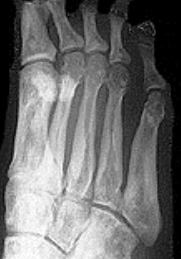

What disease is this? | Rheumatoid arthritis |

What disease is this? What does the arrow indicate? | Rheumatoid arthritis. Arrow = Bone erosion secondary to inflammation of retrocalcaneal bursa. |